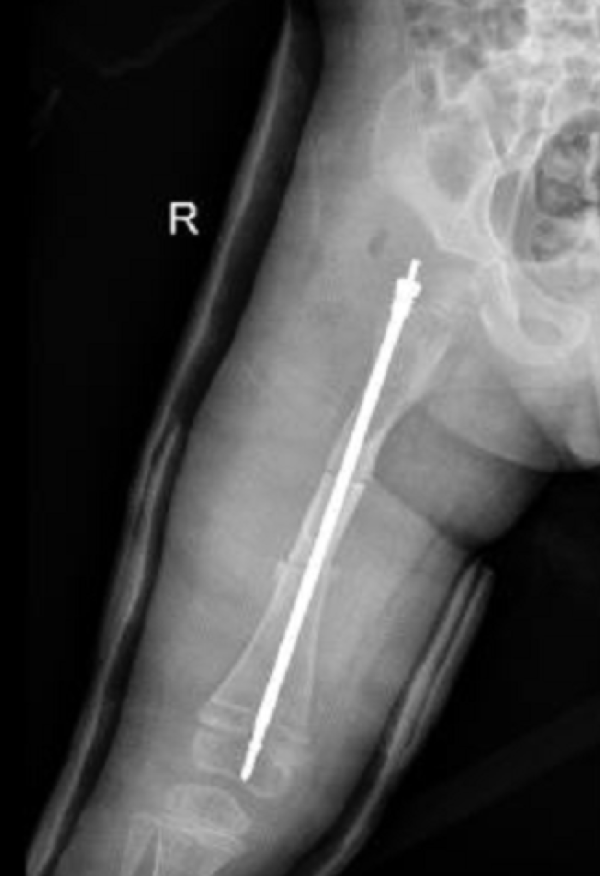

壮壮股骨内的可延长髓内钉

近日,壮壮在浙江大学医学院附属儿童医院进行了一起省内首例手术:在股骨骨髓腔内,放置可延长髓内钉,增加骨头牢度。当孩子长高时,髓内钉也会慢慢变长,一直保护着他的骨骼。

“放置可延长髓内钉,一是治疗本次骨折,二是纠正前几次骨折残留的股骨畸形,三是有效避免将来再次骨折,为孩子脆弱的骨头加一层保护。”陈建松介绍。